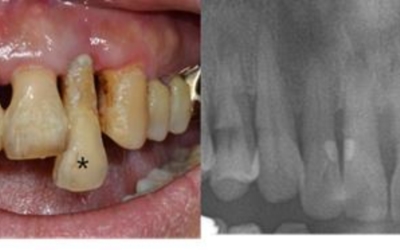

옳지 않은 형태로 자라는 사랑니는 초기엔 잇몸이 붓는 정도이지만, 나중에는 근처 어금니를 썩게 만들고 사랑니와 멀쩡한 어금니까지 통째로 발치하게 되는 불상사가 생길 수 있습니다. 사랑니의 경우 잇몸 내부쪽으로 매복해 자라는 경우도 풍부하기 때문에 치과에서 사랑니 유무를 확실히 확인할 수 있습니다.

3. 잇몸이 붓고 아플때 - 사랑니

사랑니는 치아 중 아래 위로 가장 안쪽에 나오는 어금니입니다. 사람마다 사랑니가 4개가 나는 경우가 있으며 하나가 나는 경우가 있으며, 잇몸이 붓고 아플때는 사랑니가 근처 어금니를 건드리는 옳지 않은 형태로 자라고 있을 확률이 높다고 합니다.